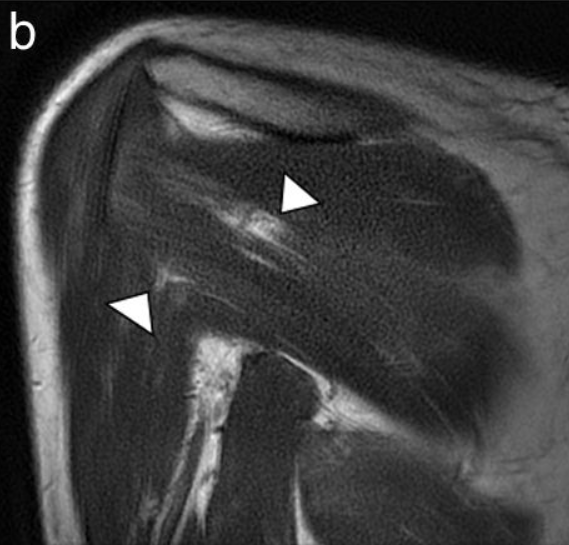

- Resonancia magnética: Cuando se sospeche de otra causa potencial (neoplasia, hernia cervical…) y nos puede mostrar si se realiza el estudio sobre la musculatura afectada. Mostrando patrones de edema difuso en fases iniciales y el aumento de infiltración grasa intramuscular en fase tardía.

Imágenes de este caso clínico